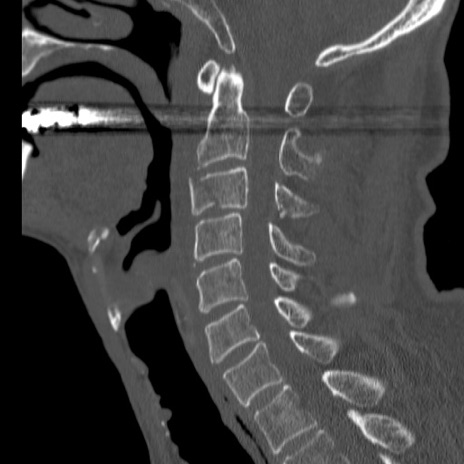

症例46 頚椎CT(矢状断像)

【症例】80歳代男性

【主訴】両側頚部〜上肢のしびれ

【現病歴】昨日、自宅内で転倒、その後より上記症状あり。意識障害なし。

【身体所見】両側上肢のallodynia(熱痛覚過敏)あり。MMTおよびDTRは正確な所見取れず。両上肢の挙上はなんとか可能。

異常所見と診断は?